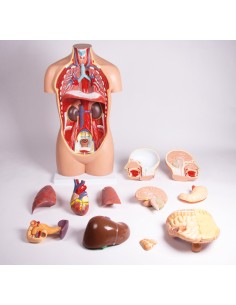

Scopri il Mondo dell’Anatomia con Modelli anatomici di Precisione

Modelli Anatomici Dettagliati per Ogni Necessità

Dal cranio in 22 parti con incastri magnetici ai modelli di colonna vertebrale, da quelli di articolazioni a quelli di cuore, ogni pezzo della nostra collezione è progettato per un’immersione totale nello studio dell’anatomia umana. I nostri modelli, realizzati tramite scansioni di ossa vere, garantiscono un’esperienza tattile autentica e una fedeltà di peso quasi identica agli originali.

Strumenti Didattici Innovativi per l’Educazione e la Pratica Medica

Essenziali per studenti e professionisti, i nostri modelli anatomici sono strumenti didattici che permettono di osservare le strutture anatomiche con precisione, eliminando la necessità di dissezioni o studi invasivi. Sono inoltre utili per spiegare ai pazienti le patologie, rendendo la comunicazione più efficace e risparmiando tempo prezioso.